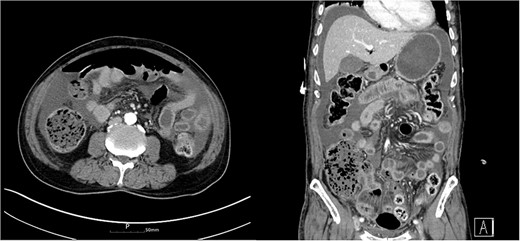

Three days after discharge, he presented to the emergency room with severe abdominal pain. He did not have bowel movement for a week. He had severe constipation and frequently dug up the stool with his fingers. A physical examination revealed abdominal distension and rigidity with rebound tenderness. The patient’s blood pressure was 110/70 mmHg, pulse rate was 116 beats/min and body temperature was 38.0°C. In the complete blood count, a white blood cell count was 2.04 × 103/mm3 and hemoglobin was 13.5 g/dL. The C-reactive protein was 34.33 mg/dL, procalcitonin was 14.50 ng/mL and creatinine was 1.79 mg/dL. He underwent computed tomography (CT), which showed focal bowel wall defect at the distal ileum, and complicated fluid collection and free air in the abdominal cavity (Fig. 2). The patient was diagnosed with small bowel perforation due to fecal impaction and underwent emergency surgery.

Abdomen CT showed complicated fluid collection and free air in the abdominal cavity.